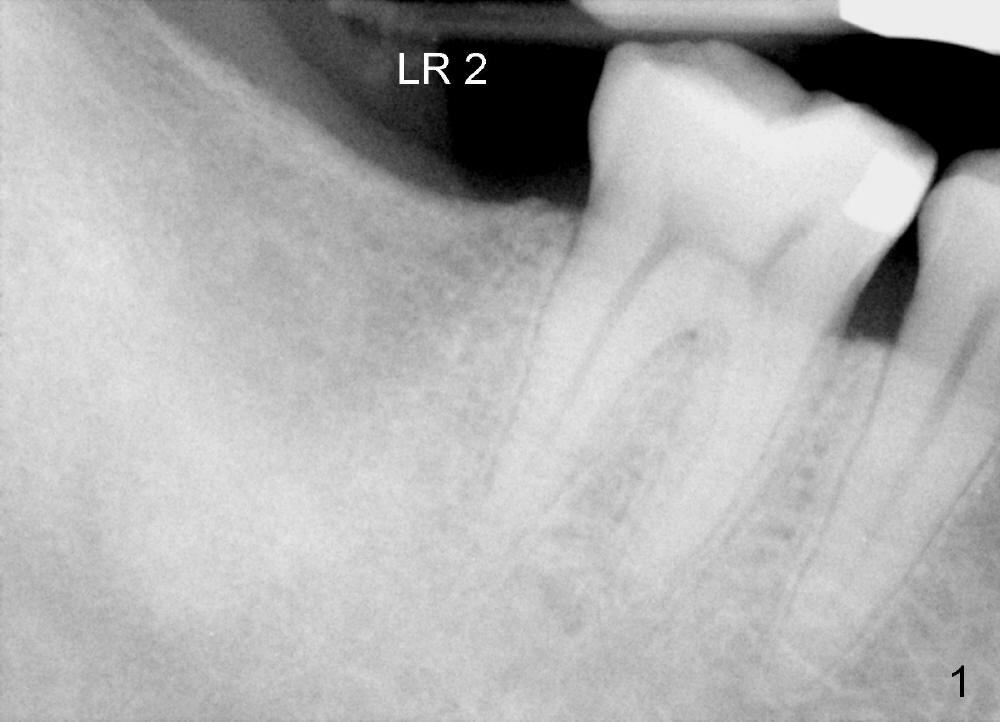

A 53-year-old man requests implant restoration for the lower right 2nd molar (Fig.1: LR2). A 5.3x14 mm submerged tapered implant is planned (Fig.2). PA is taken with a parallel pin after use of a 2 mm drill at the depth of 12 mm (Fig.3). It appears that the length of 14 mm has a safe margin (2-3 mm from the inferior alveolar nerve, yellow dashed line). In addition, the distance from the distal surface of the 1st molar is within normal limit (~5 mm).